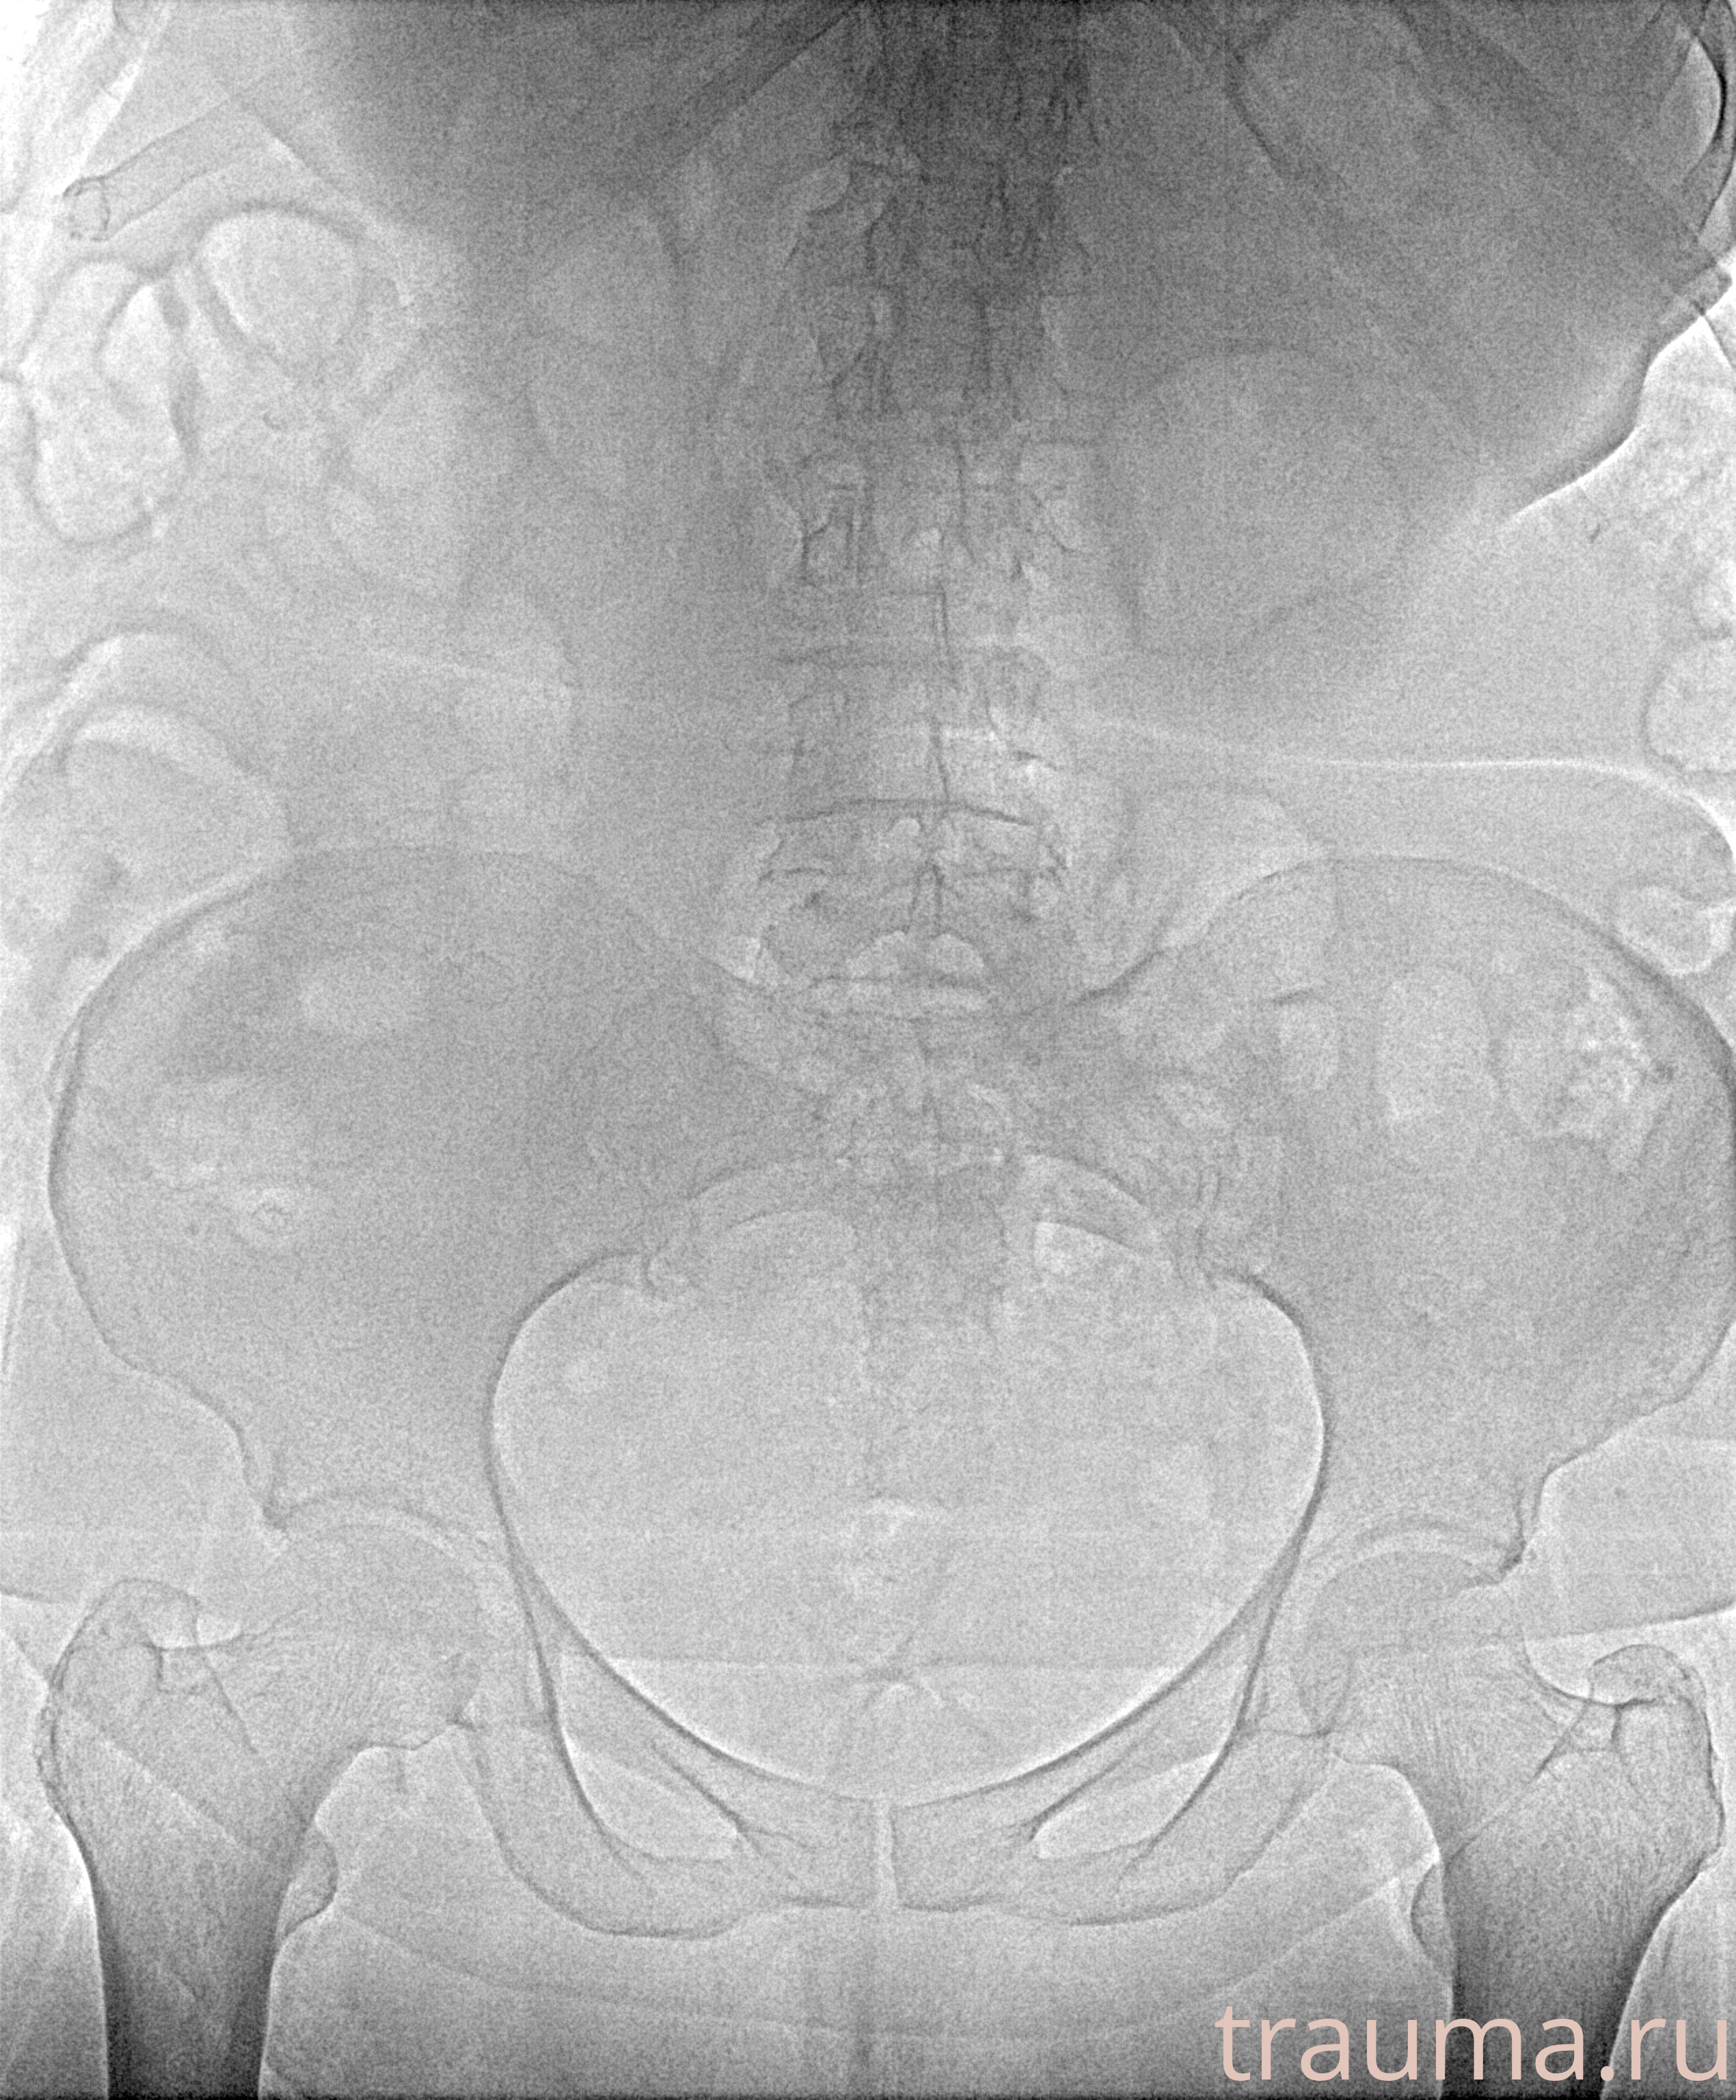

Рентгенограммы

Рентген на дому: по вашему адресу приезжает врач-рентгенолог, травматолог-ортопед с мобильным рентгеновским аппаратом, проводит диагностику травмы или заболевания, делает необходимые рентгенограммы, дает рекомендации по дальнейшему лечению. Получить качественные снимки в домашних условиях возможно благодаря уникальной методике, разработанной МосРентген Центром для института  Склифосовского